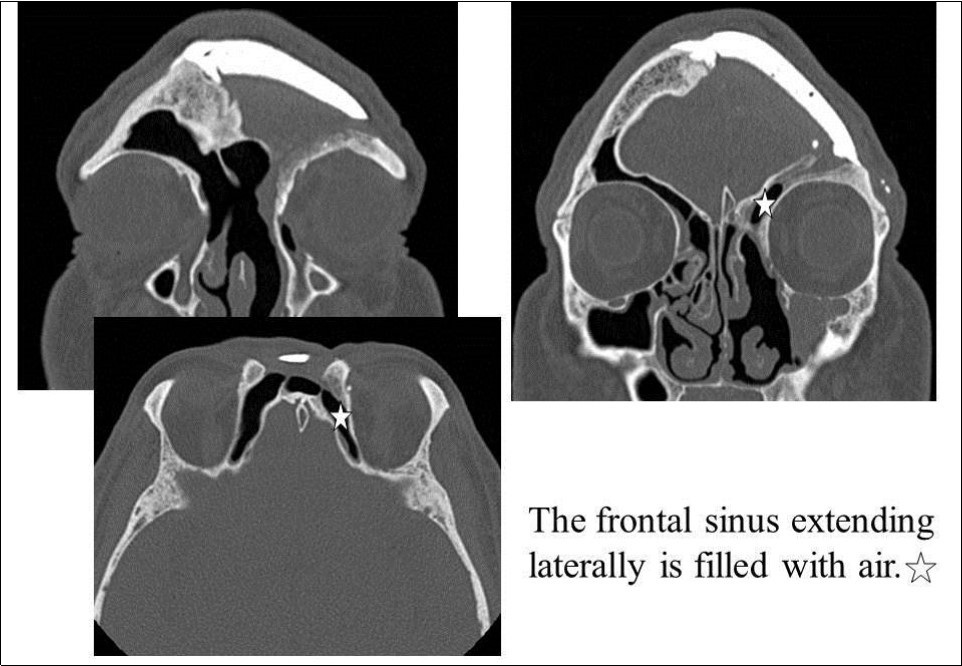

Recurrent frontal sinusitis was suspected, and the patient was referred to our department for evaluation on February 14, 2007. On initial evaluation, the left upper eyelid swelling was resolved; however, paranasal sinus computed tomography (CT) showed two left frontal sinus cysts (Figure 1). The patient had a history of hypertension that was well-controlled on oral medications. No other major disorders were present, including diabetes or heart disease.

Figure 1.CT of the paranasal sinuses showed two left frontal sinus cysts. Black arrows: ceramic implant. Black stars: two left frontal sinus cysts

CT of the paranasal sinuses showed two left frontal sinus cysts. Black arrows: ceramic implant. Black stars: two left frontal sinus cysts

On April 16, 2008, reoperation was performed to place a ceramic implant, but some pus was found in the left lateral sinus. The lesion was debrided, the dead space was filled with muscle, and surgery was completed without ceramic implantation. On October 17, 2008, another surgery confirmed that the frontal sinus was clean, and a ceramic implant was placed. The postoperative course has been good, and as of May 2009, the frontal sinus extending laterally is filled with air (Figure 5, Figure 6).

Figure 5.Paranasal sinus CT after the last surgery. White star: The frontal sinus extending laterally is filled with air.

Paranasal sinus CT after the last surgery. White star: The frontal sinus extending laterally is filled with air.